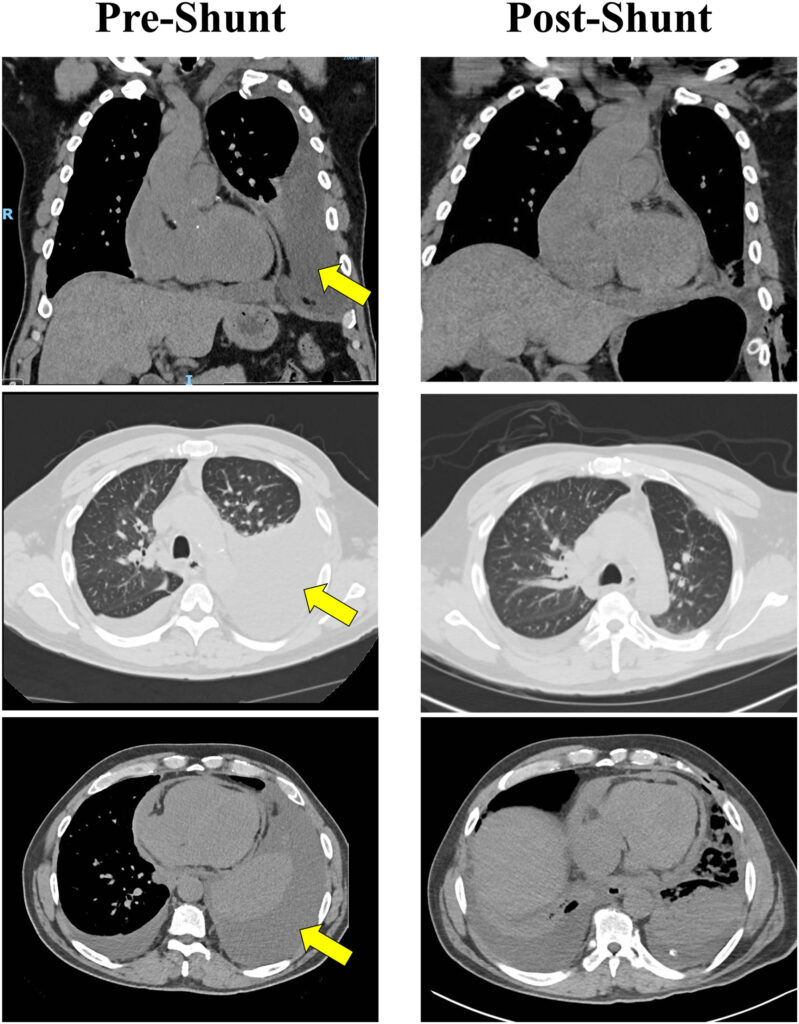

Na internação atual para a realização do shunt, a tomografia de tórax mostrou um derrame pleural importante com colapso total do lobo inferior esquerdo do pulmão, bem como documentou a presença de um derrame pericárdico leve a moderado.

Volume 10 Number 1